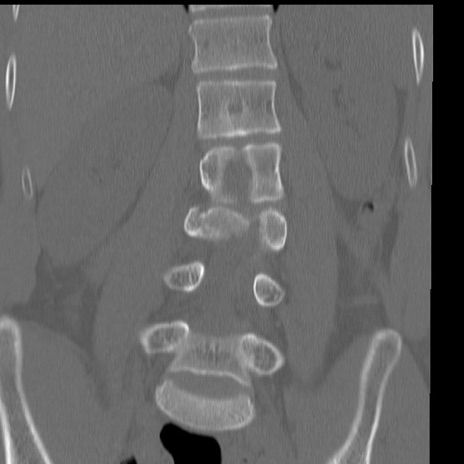

症例3 腰椎CT(冠状断像)

腰椎CT

横断像